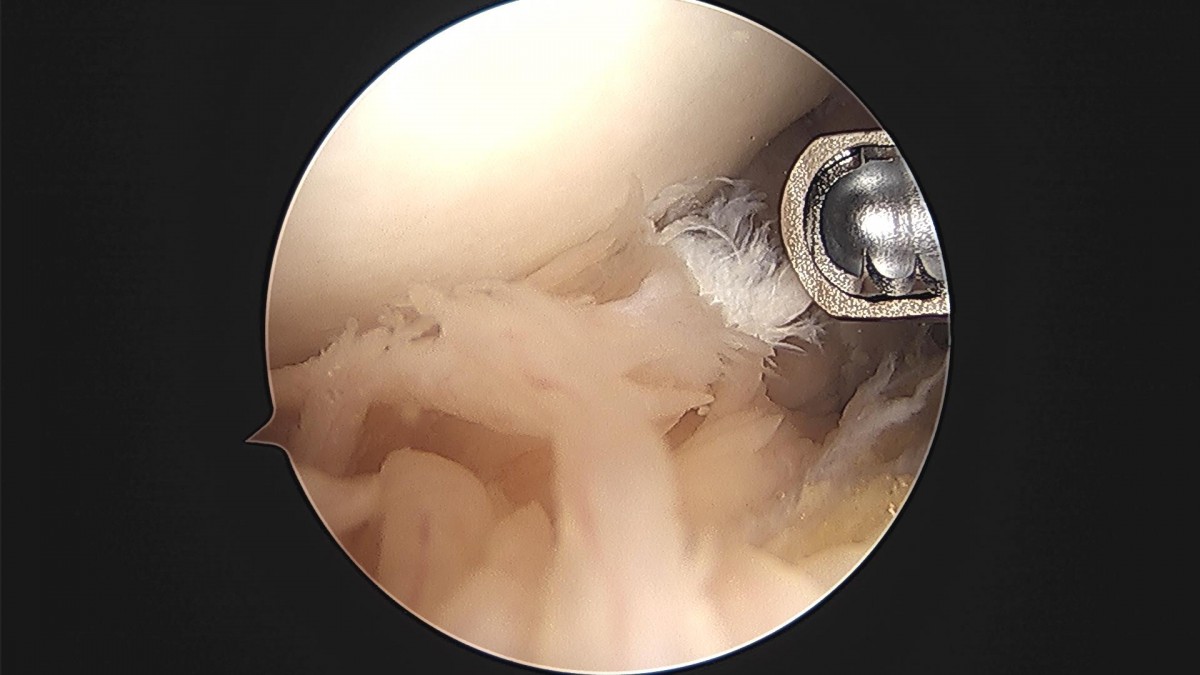

배우한 원장님 무릎 반월상 연골판 절제술 이순O 환자

작성자 최고관리자 댓글 0건 조회 1,013회 작성일 23-08-02 11:45